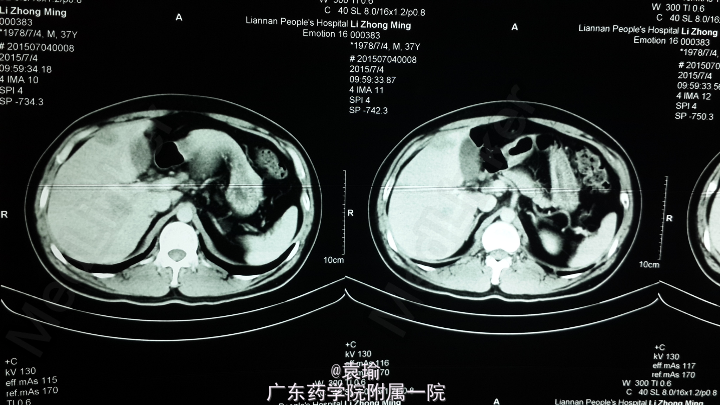

辅助检查:多次血常规检查见嗜酸性粒细胞计数及比例增高(见附图),肝功能检查异常(见附图),超敏C反应蛋白6.200mg/L,降钙素原0.076ng/ml,余大、小便常规正常,多次大便找虫卵阴性,肾功能、凝血功能、血脂均正常,肿瘤指标(AFP、CEA、Ca-199、CA-125、CA-724、CA-153)均正常,胃镜检查示非萎缩性胃炎轻度,多点活检未见明显嗜酸性粒细胞浸润。腹部MR+MRCP:肝内多发异常信号影,考虑感染性病变,注意寄生虫感染可能,MRCP未见异常。

该病例急性起病,影像学检查见肝内多发占位性病变,对占位病变的性质不确定,结合多次血常规检查嗜酸性粒细胞明显增多,且患者有进食“鱼生、螺肉”等流行病学史,故高度怀疑寄生虫感染可能,但因进一步确诊存在困难,遂予诊断性治疗,短期内血常规好转,支持诊断。 提出该病例,请各位有相关治疗经验的同道对诊治过程进行指正,了解有无其他可明确诊断方法,并对进一步治疗提出指导意见,多谢!